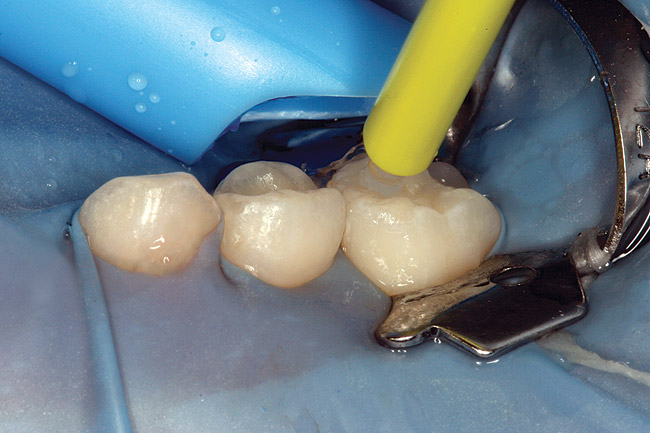

Figure 6  Rubber dam and wedge in place.

Figure 7  Matrix in place showing extrusion of hydrochloric acid.

Figure 7

Figure 8  Rinsing of hydrochloric acid after removal of matrix.

Figure 8

Figure 9  Placement of needle tip to allow 1-minute treatment with alcohol dessicant.

Figure 10  Icon Infiltrant flowing through matrix channel into contact area on mesial of tooth A.

Figure 11  Light curing of infiltrant material.

Figure 12  Final view showing treated surface of mesial of tooth A.